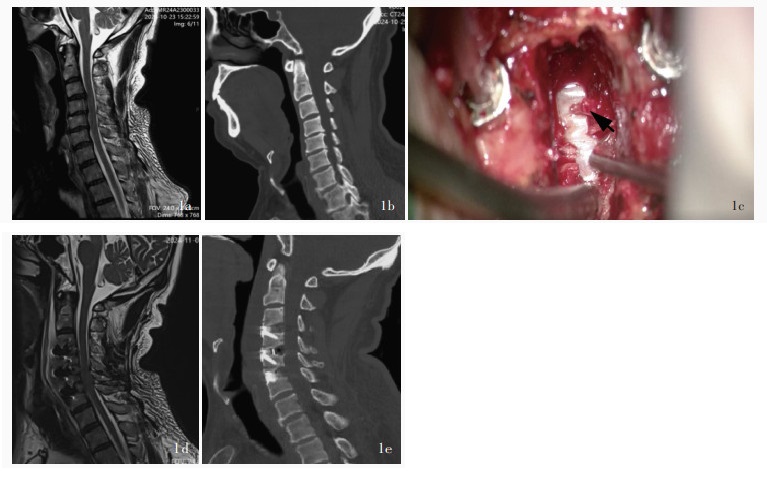

Chen X , Wang G , Qin YT , Li J , Wang P , Huang W , Chen J . Clinical significance of microsurgical excision of the posterior longitudinal ligament using a high-frequency electrosurgical excision procedure in anterior cervical discectomy and fusion. Wideochir Inne Tech Maloinwazyjne, 2019, 14: 575- 580.